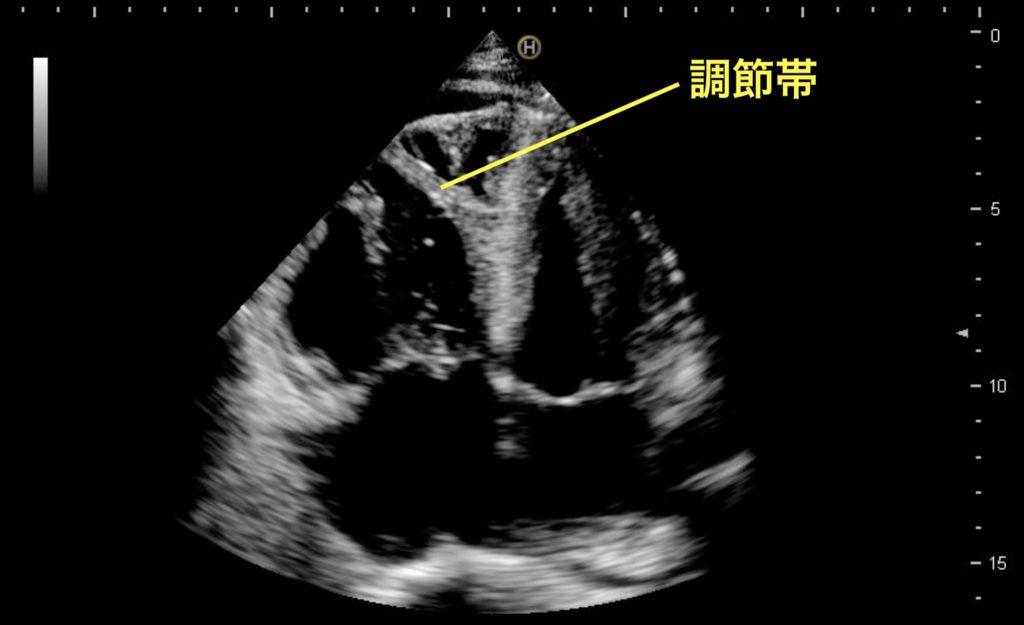

右心の拡大、肉柱の発達

心尖部四腔像は、右室と左室のサイズを比較するのに適している。右室幅が左室幅の6割以上となっていれば右室の拡大があると評価でき、この例のように右室:左室が1:1以上となっている場合は明らかな異常である。右室内の肉柱が発達していることから、何らかの慢性右心負荷が生じていることが示唆され、急性の病態が生じているか否かはこの所見からだけでは判断が難しい。また、プローブの向きが反対になっている場合、画面左側に左室が映ってこの例と類似の像を呈するが、右室内心尖部寄りを横断する調節帯(Moderator band)の存在によって右室と左室の判別が可能である。本例では右室収縮の指標であるTAPSEも低下していることが目視で認識できる。(関連動画:#87)